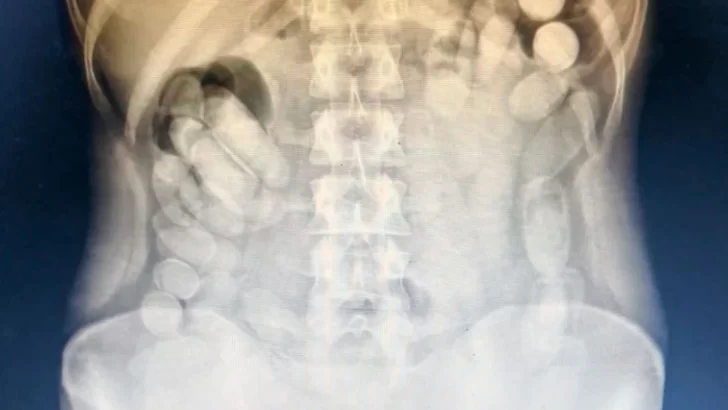

Fue internada en el Centro de Salud

Detuvieron a una mujer que transportaba 106 cápsulas de cocaína en el estómago